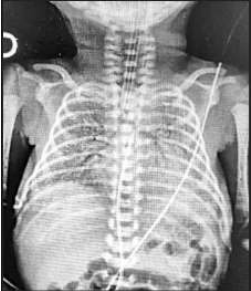

Lactente masculino de 14 meses está internado em enfermaria de pediatria para tratamento de uma pielonefrite

aguda, por meio de antibiótico venoso. Solicitada ultrassonografia renal e de vias urinárias que evidenciou, apenas,

hidronefrose bilateral. A mãe do menor relata outros dois internamentos prévios pelo mesmo diagnóstico (o que foi

comprovado pelos resumos de alta). Paciente recebeu alta com quimioprofilaxia oral e solicitação para

realizar uretrocistografia miccional (UCM) em nível ambulatorial, desde que urocultura negativa.

A UCM foi realizada, e uma das imagens encontra-se abaixo:

Sobre este caso, analise as assertivas abaixo:

I. A quimioprofilaxia foi bem indicada na alta hospitalar, e uma das opções é o emprego de sulfametoxazol e trimetoprima na posologia de um quarto da dose terapêutica, uma vez ao dia.

II. A imagem da UCM evidencia achados típicos de válvula de uretra posterior.

III. A cintilografia renal com ácido dimercaptosuccínico-tecnécio-99 deve ser solicitada, pois a principal hipótese diagnóstica para este lactente é de estenose da junção ureteropélvica à direita e displasia renal à esquerda.

IV. A hipótese mais provável para este paciente é de estenose da junção ureterovesical à direita e megaureter à esquerda.

Podemos afirmar que